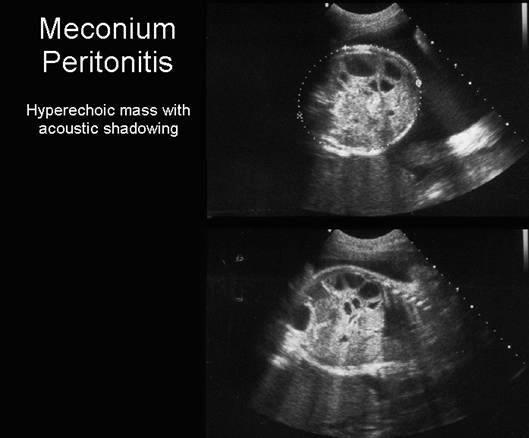

Meconium Peritonitis

Meconium Peritonitis

Meconium Peritonitis

What can obstructed bowel cause?

perforation and infection

What is the sonographic appearance of meconium ileus?

echogenic small bowel